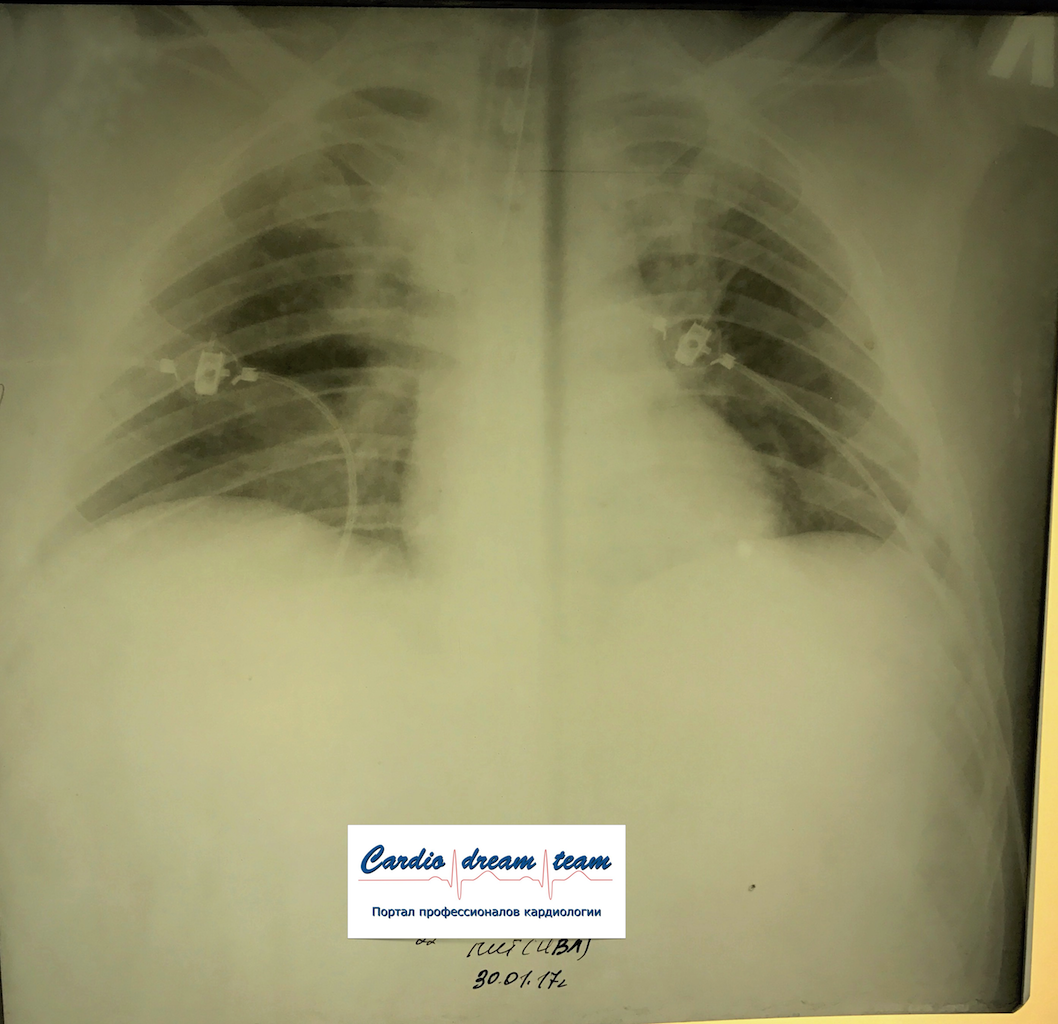

М 35 лет наркоман. Аспирация рвотных масс. До санации и после.

IMG_5519.png

IMG_5519.png [ 1.46 MiB | Просмотров: 12424 ]